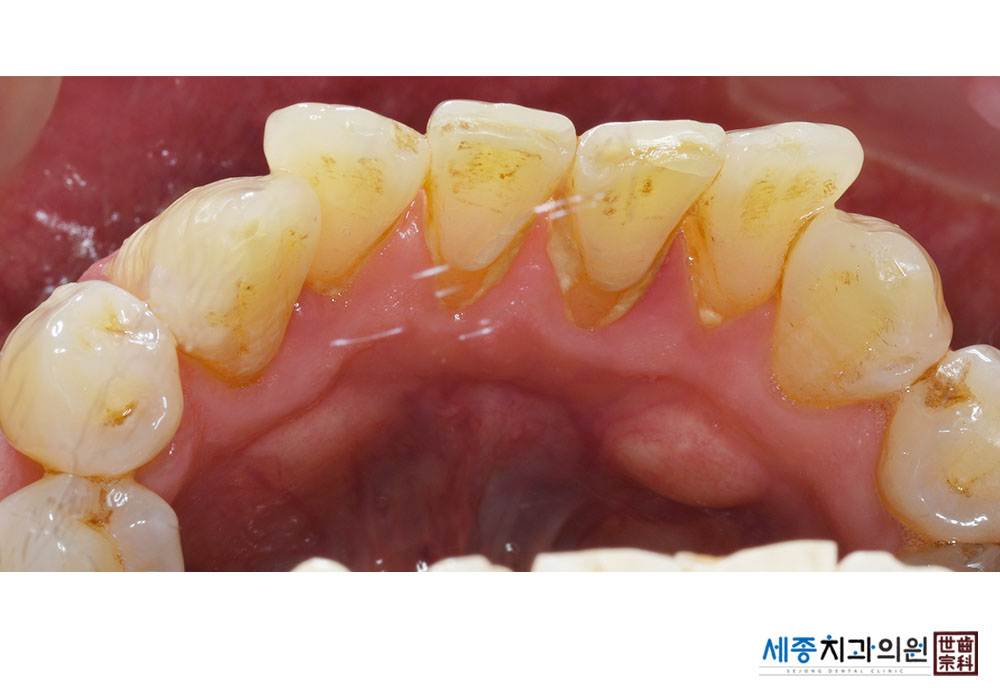

[스케일링] 치주질환 예방 스케일링

치료전 : 2023-06-29

치료후 : 2023-06-29

가글마취&저주파 스켈러를 사용한 스케일링